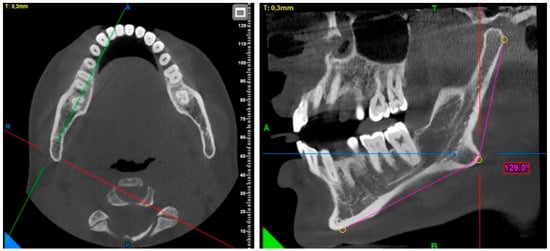

2. Materials and Methods